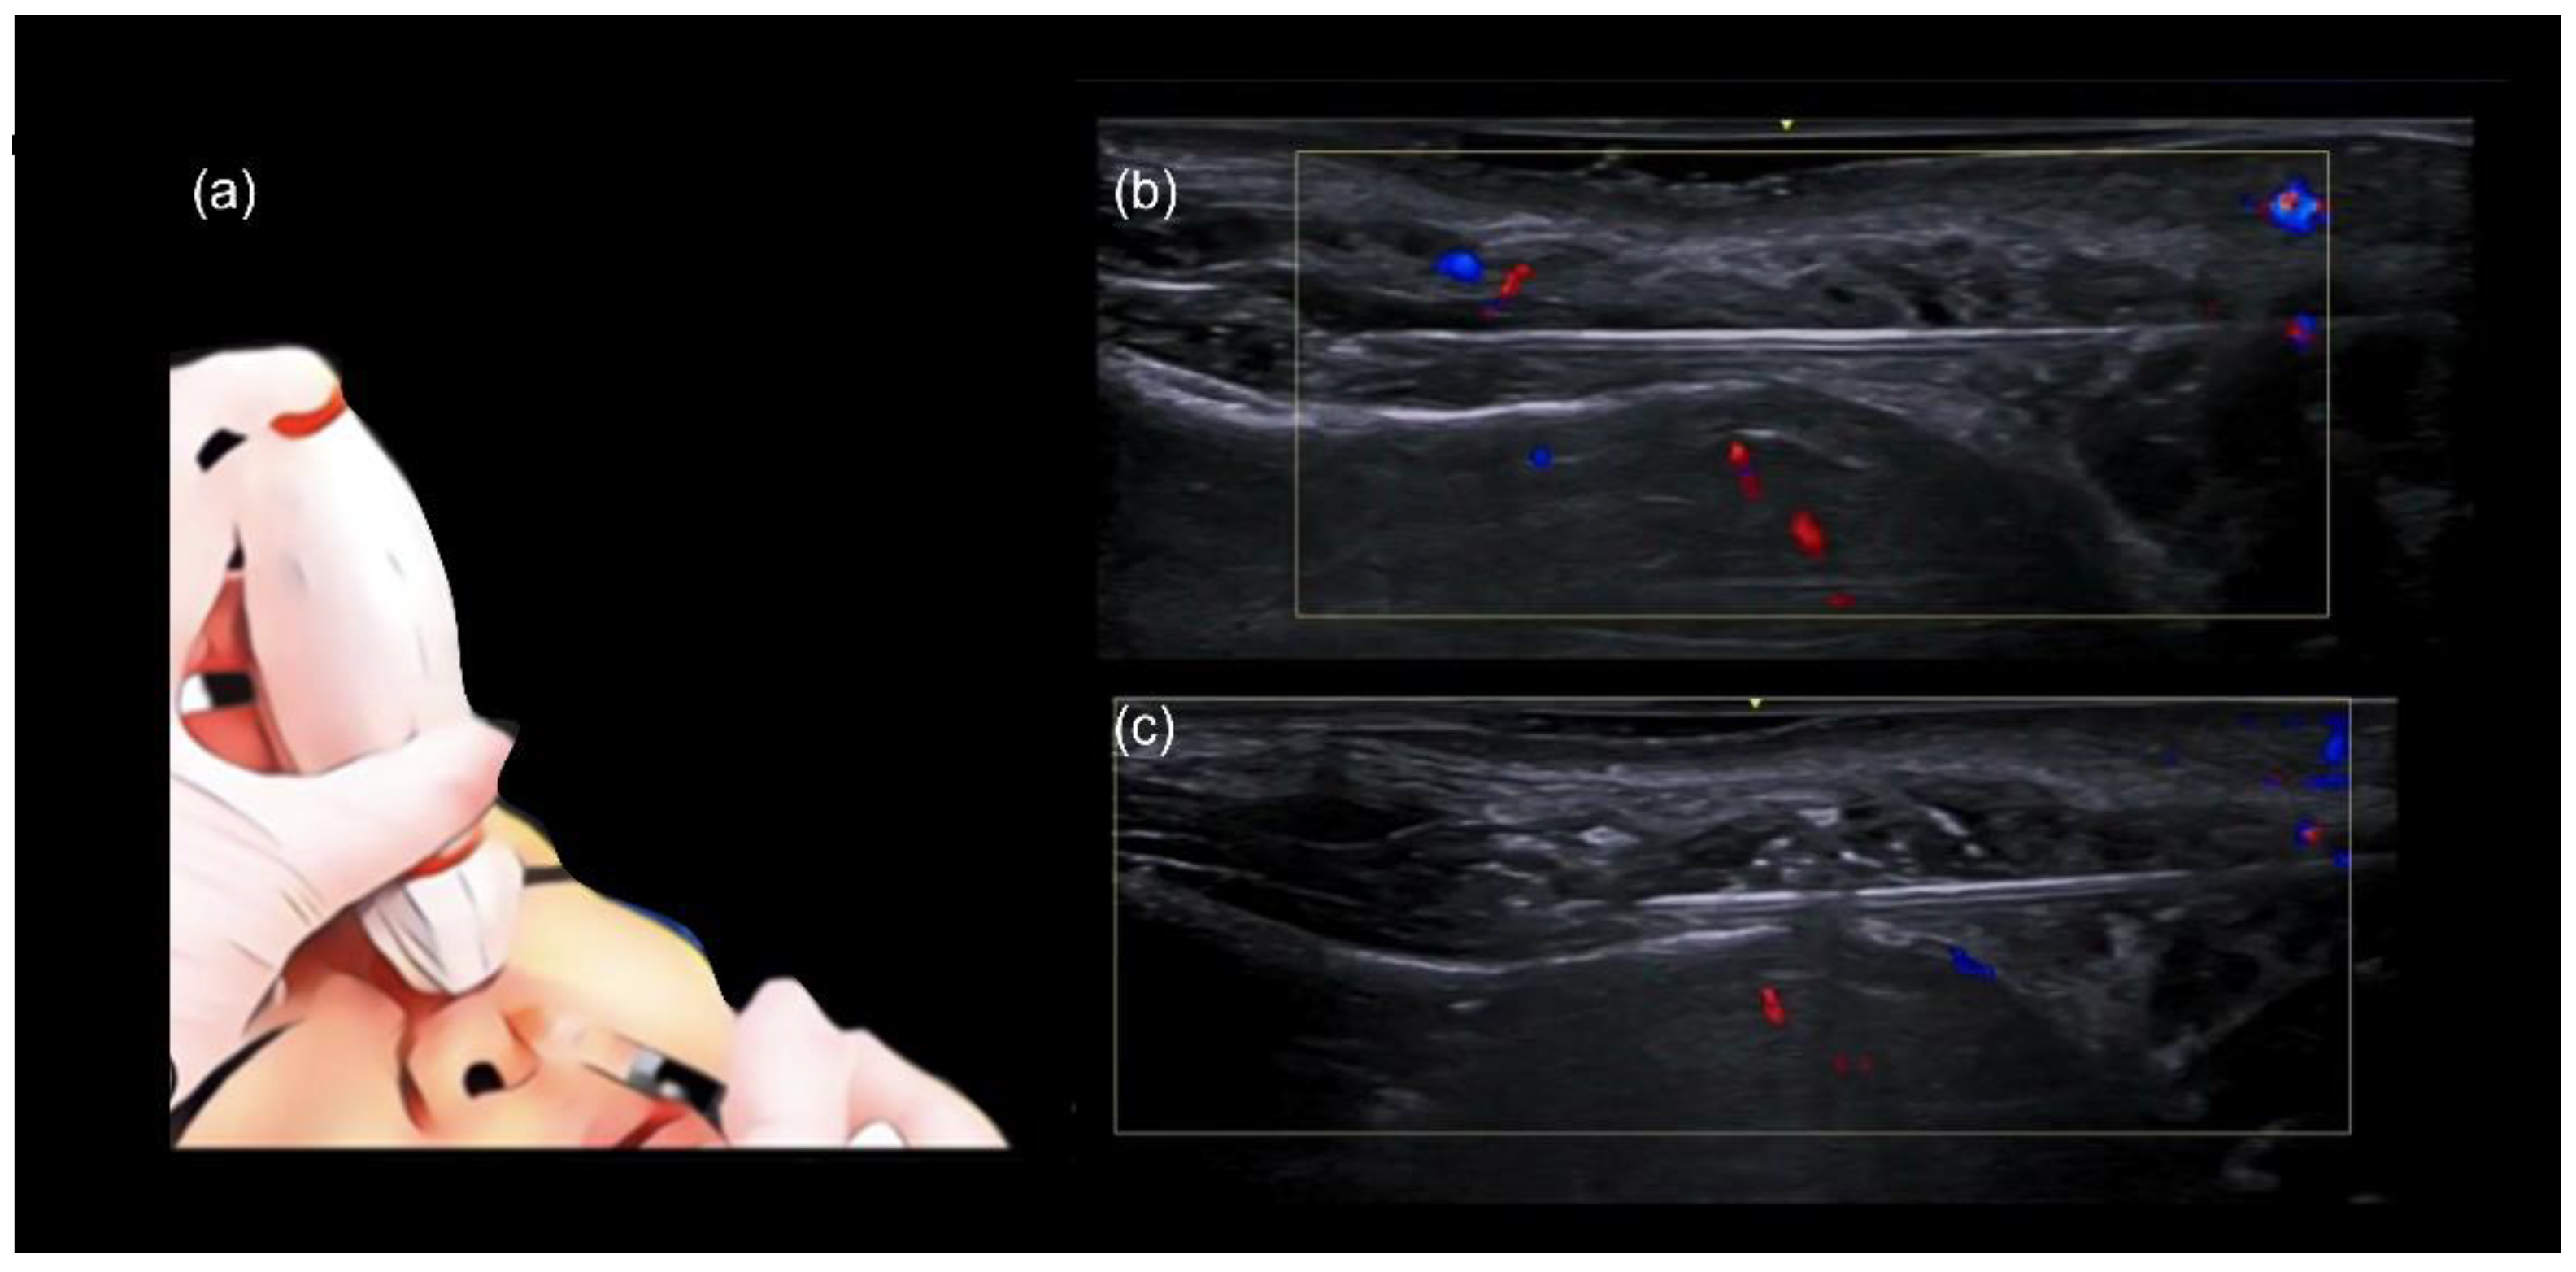

Once the cannula is correctly positioned in the deep tissue plane, an ultrasound probe, with a small amount of sterile gel, is placed along the cannula (in-plane technique). After confirming the cannula tip is in the correct position, away from blood vessels and within the appropriate tissue plane (Figure 2), the filler is injected slowly in a linear retrograde fashion under ultrasound guidance (Figure 3a–c).

Figure 3.

Scan while injecting in the nose. (a–c) Color Doppler US with a 20 MHz probe demonstrates the in-plane technique in the dorsum, which allows real-time visualization of the cannula as filler is being deposited in a linear retrograde fashion. (a) Injection technique using a blunt cannula 25 G. Here we demonstrate the” scan while injecting” technique in the nose. (b) Plane of injection is checked for vessels. (c) Filler starts to be deposited.